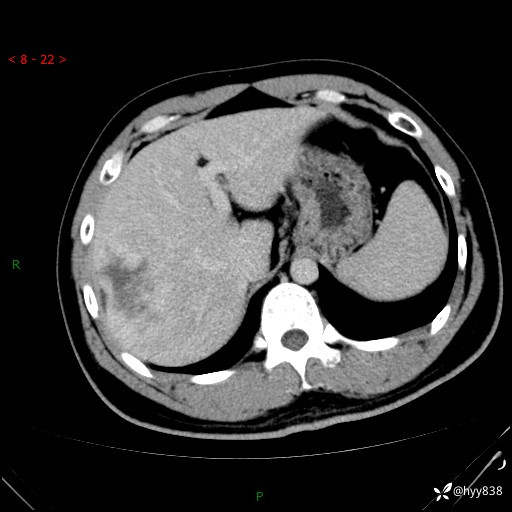

增强动脉期

img